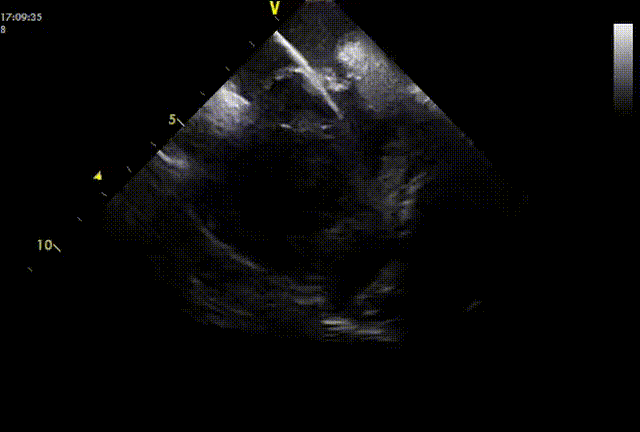

导丝通过PFO